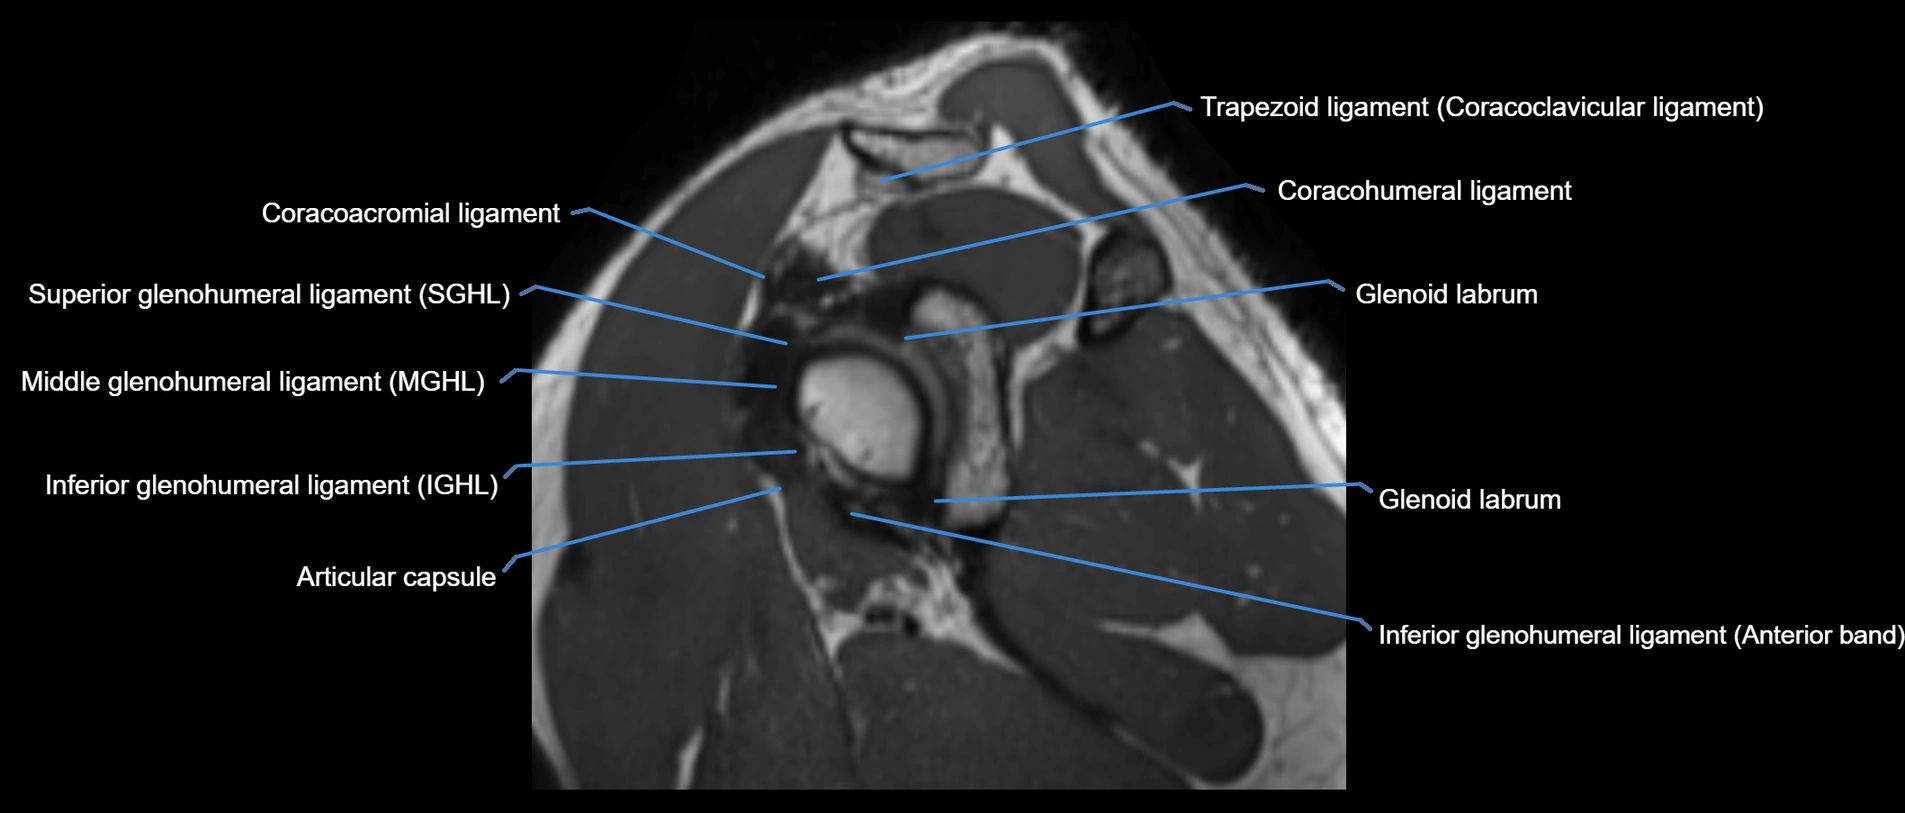

MRI images

image